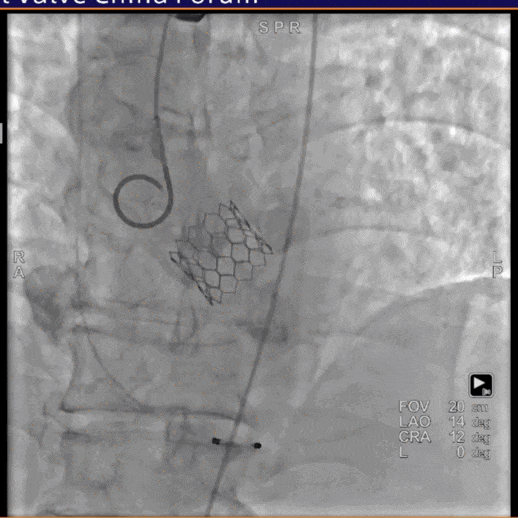

术中经右侧股动脉入路,使用19mm球囊预扩,顺利植入23# RENATUS®球扩式经导管主动脉瓣,瓣膜释放位置理想、形态及功能良好,无外周血管损伤,术后无瓣中及瓣周反流等并发症。

术中通过心内、心外联合高效协作,经右侧股动脉入路,使用17mm球囊预扩,成功植入21# RENATUS®球扩式经导管主动脉瓣,输送器顺利通过,瓣膜精准释放,术后即刻平均跨瓣压差由80mmHg降至8mmHg,术后峰值流速由5.6m/s降至2.0m/s。瓣膜释放位置理想、形态及功能良好,无外周血管损伤,术后无明显瓣中及瓣周反流等并发症。

手术经右侧股动脉入路,使用19mm球囊预扩,术中植入23# RENATUS®球扩式经导管主动脉瓣。输送器顺利通过,瓣膜精准释放,术后即刻平均跨瓣压差由48mmHg降至5mmHg,术后峰值流速由4.6m/s降至2.0m/s。瓣膜释放位置理想、形态及功能良好,无外周血管损伤,术后无明显瓣中及瓣周反流等并发症。

术中造影